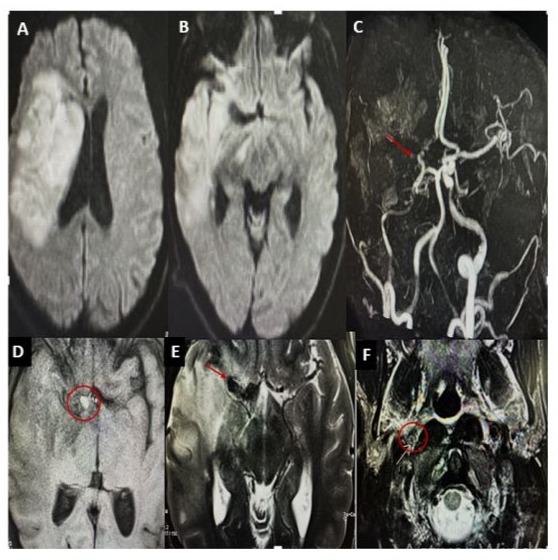

H.E a 26-year-old man with a history of active smoking, cannabis use, and chronic alcohol consumption. He had no history of recurrent tonsillitis, childhood heart disease, autoimmune disorders, known hereditary diseases, cervical trauma, or heavy lifting. He was admitted to the neurological emergency unit 3 days after sudden onset of proportional left hemiplegia, dysarthria, and Claude Bernard-Horner syndrome. An urgent brain CT scan revealed an ischemic stroke in the middle cerebral artery territory with a hyperdense sylvian artery sign (Figure 1). Brain MRI showed an intracranial dissection of the right carotid and sylvian arteries (Figure 2). One week later, digital subtraction angiography revealed a pseudoaneurysmal dilation at the origin of the right sylvian artery, resulting from the progression of the intracranial dissection (Figure 3). The patient was placed on antiplatelet therapy. The etiological assessment of his ischemic stroke revealed mitro-aortic infective endocarditis complicated by an abscess of the membranous septum, severe aortic regurgitation, and moderate mitral regurgitation. Notably, his initial Transthoracic Echocardiography (TTE) six days prior revealed infected endocarditis without concomitant valvulopathy. Blood cultures were negative. Biological analyses showed absence of inflammatory syndrome with negative Procalcitonin, positive TPHA and VDRL serology in the blood, while Cerebrospinal Fluid (CSF) analysis revealed a clear, normotensive fluid with normal biochemical and bacteriological findings and negative TPHA and VDRL serology in the Cerebrospinal Fluid (CSF), the other serologies (serology of hepatitis B and C, HIV) were negative. The patient received intravenous antibiotic therapy with ceftriaxone (2g/day) for six weeks and gentamicin (160mg/day) for two weeks, with an indication for valve replacement surgery. Neurological deficits partially regressed (NIHSS at first day=9, at one month=5, and at three months=2, with a modified Rankin Scale score of 3 at three months).

Figure 2: Brain MRI shows a right fronto-temporo-parietal hypersignal with mass effect on the ipsilateral ventricles (A–B). Magnetic resonance angiography (MRA) reveals total occlusion of the right middle cerebral artery (MCA) and hypoplasia of the right internal carotid artery (ICA) and the A1 segment of the anterior cerebral artery (C). A nodular formation, hypointense on T2-weighted images and hyperintense on T1-weighted images, is observed at the level of the carotid terminus (D–E). A hyperintense crescent on T2weighted imaging, consistent with an intramural hematoma, is also visible (F).